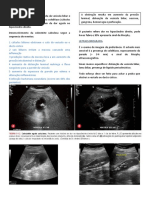

Esame radiologico nella gotta

Lesioni radiologiche evocatrici di gotta sono riscontrabili quasi esclusivamente a livello dei

piedi e delle mani. Tipico l'aspetto a geode, particolarmente evidente in corrispondenza

delle articolazioni MTF (specie la prima), dellIF dellalluce e delle mani. Si tratta di

unipertrasparenza ossea a stampo, rotonda od ovale, di dimensioni variabili, unica o pi

frequentemente multipla, con bordi ben definiti, situata in posizione centrale o periferica.

Se le cavit sono multiple, possono restare separate o entrare in comunicazione tra loro,

con aspetto a nido dape. Affiorando alla superficie ossea, il geode pu usurare la

corticale fino a interromperla, si ha cos unerosione della corticale. Nel tempo si giunge ad

ampie erosioni e distruzioni ossee con aspetti cosiddetti a scoppio.